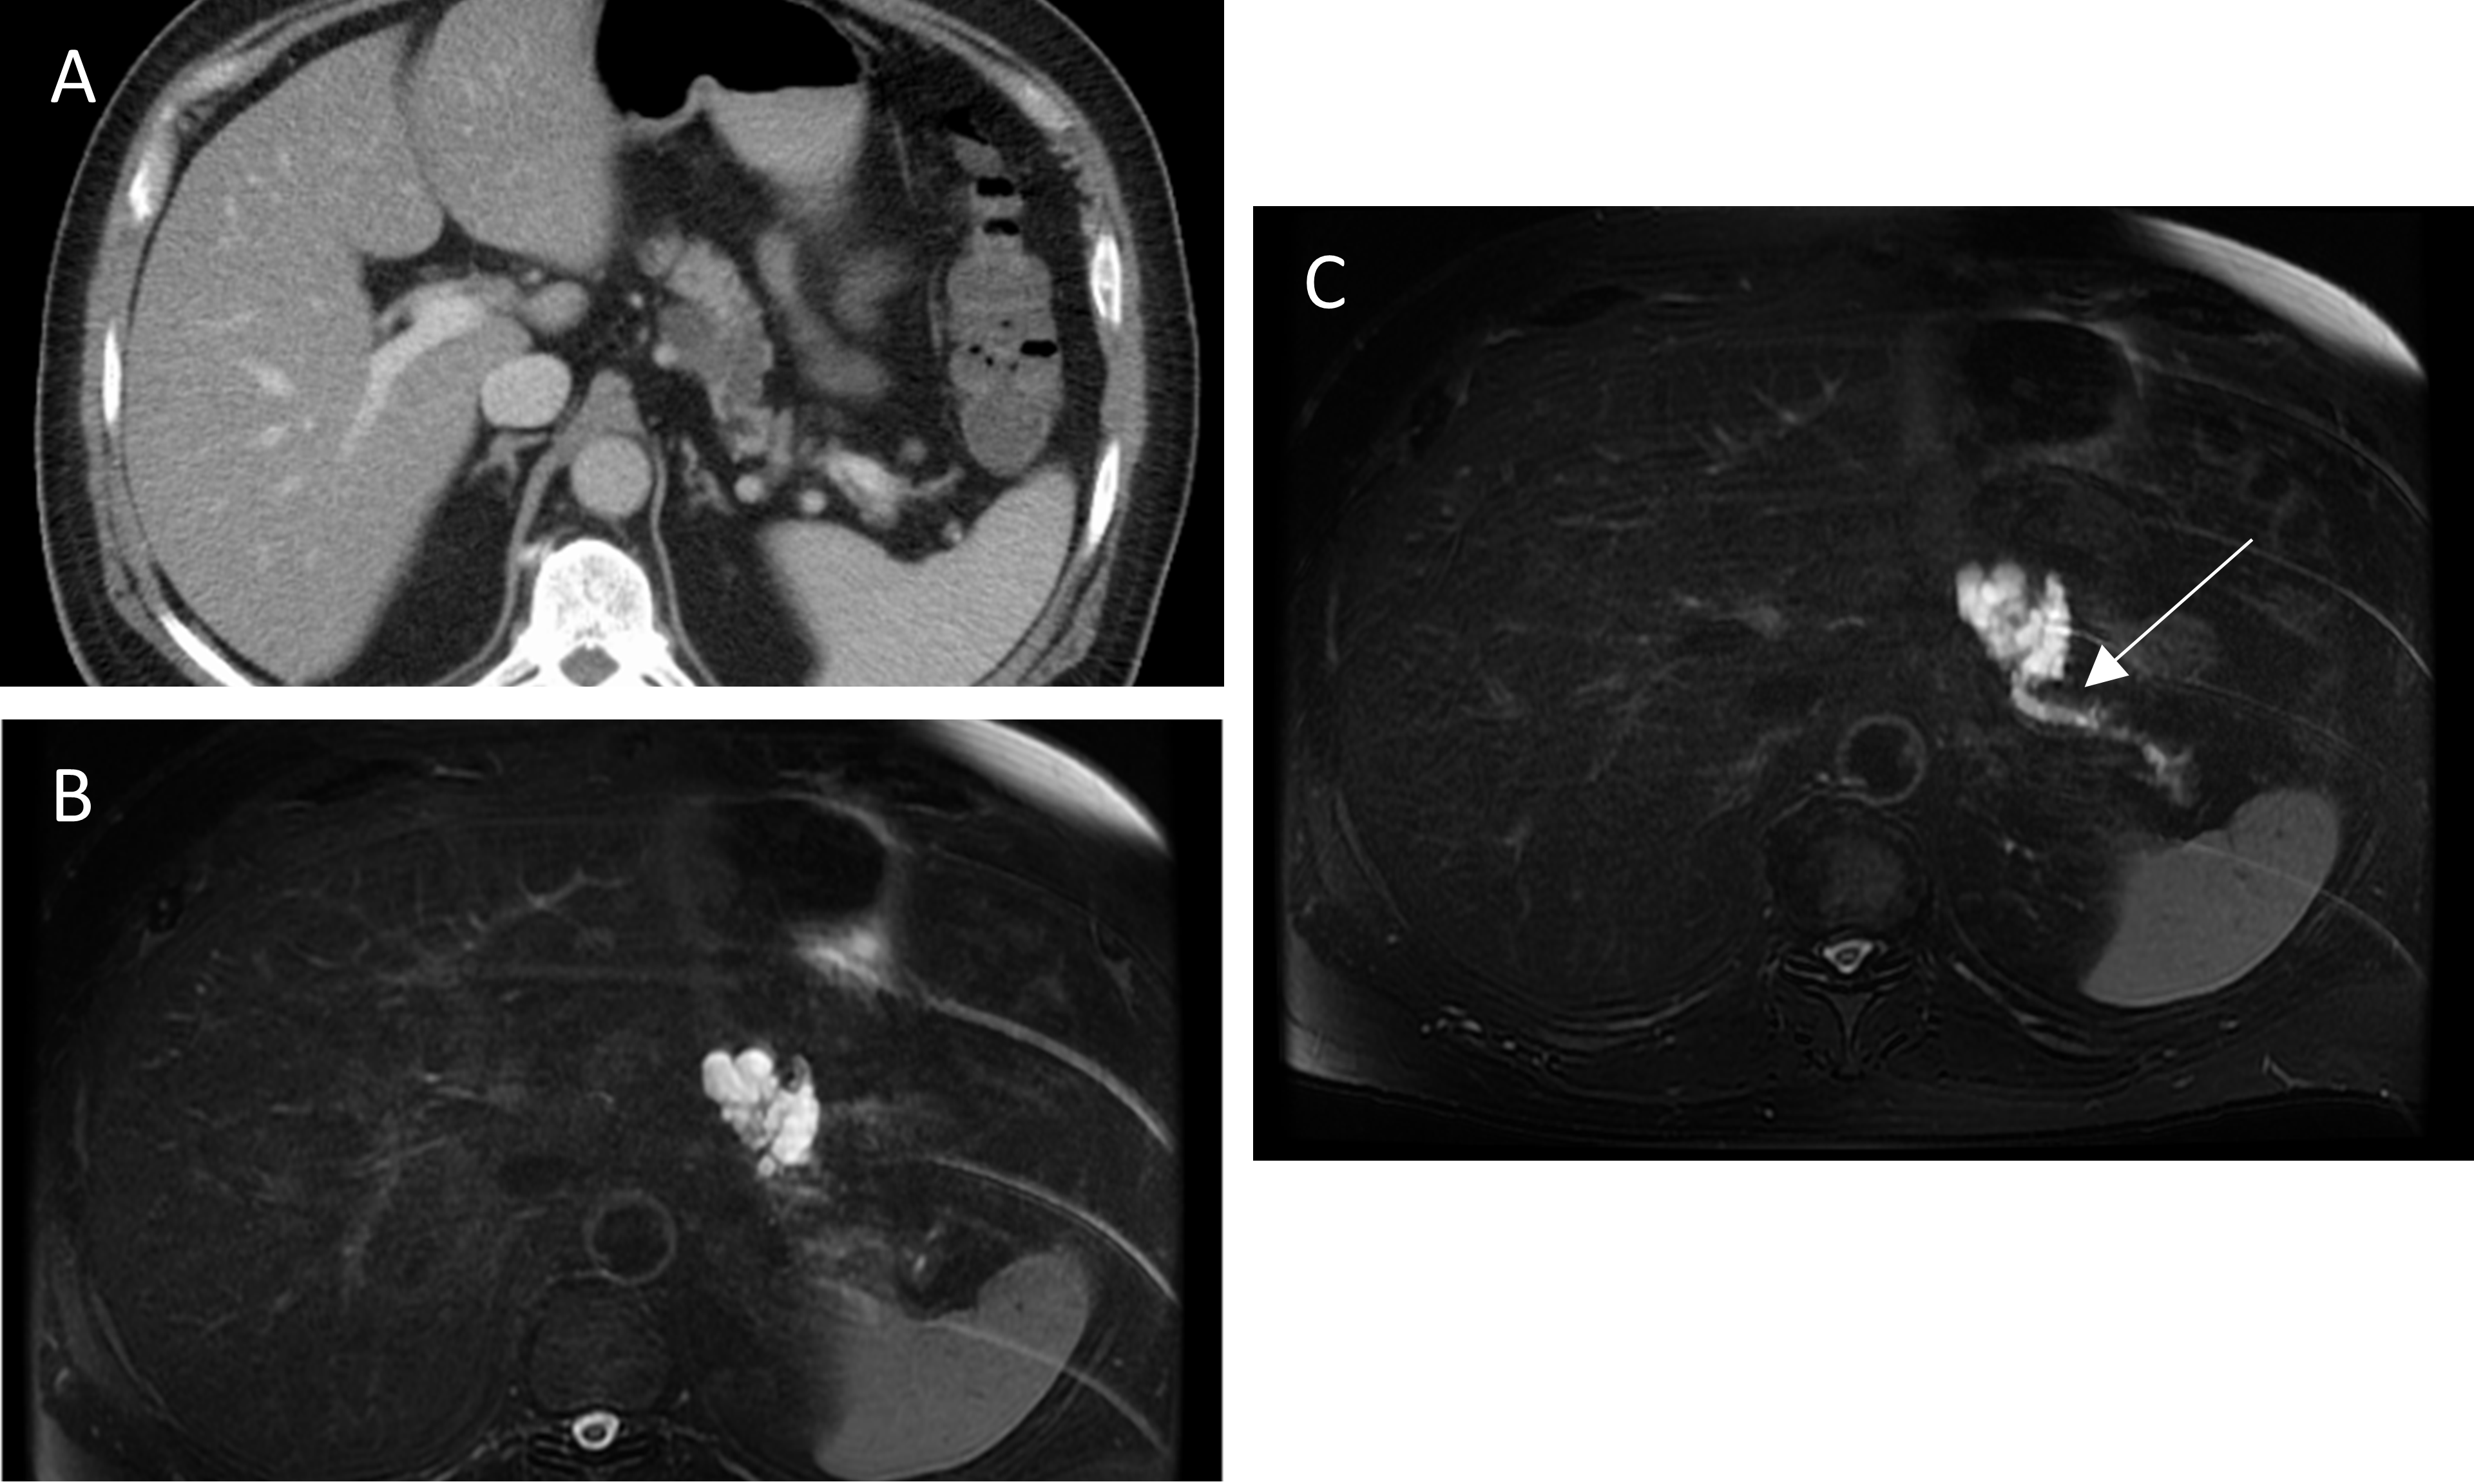

Management of Cystic Neoplasms of the Pancreas

- Updated guidelines for pancreatic cyst management have recently been released, including the 2018 European Consensus Guidelines, the 2017 American College of Radiology Guidance, and the 2016 Revisions to the International Consensus Guidelines.

- Epithelial histologic subtypes of intraductal papillary mucinous neoplasms have been shown to have important implications for prognosis.

- Pancreatic cyst fluid analysis for DNA biomarkers has shown promise for cyst diagnosis and detection of malignancy in the PANDA clinical trial and other studies although utility in clinical practice has not been demonstrated.

- A multidisciplinary team at Johns Hopkins Hospital published details of their multidisciplinary pancreatic cyst clinic outcomes, the first of its kind reported in the literature.